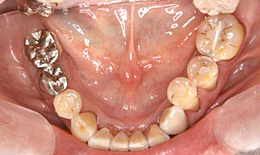

インプラント症例(8)72歳 男性

治療後

下顎

保存困難な歯を抜歯後、インプラントを2本埋め込んで、セラミックスクラウンを被せた